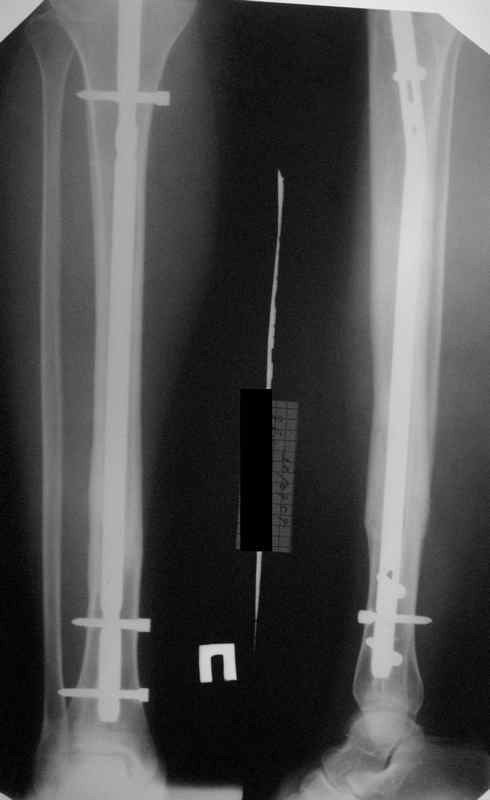

Все наши сомнения связаны с тем, что этих незначительных погрешностей (небольшой вальгус, неглубоко пробит гвоздь, мало запирающих винтов в

дистальном отломке) не одна, а несколько, и вместе они могут значительно осложнить дальнейшую жизнь пациенту. В нашей практике были подобные случаи, при которых после разрешения полной нагрузки либо начинала увеличиваться деформация, либо происходил перелом гвоздя по ближайшему отверстию. Кроме того, при диафизарных переломах, имея в арсенале надежный фиксатор, нет никакой необходимости вынуждать пациента ограничивать нагрузку на ногу в течении 2-3 месяцев.

Взвесив все <<за>> и <<против>>, мы приняли решение и выполнили реостеостинтез: выбили гвоздь до линии перелома, провели отклоняющую

спицу, забили обратно гвоздь и заблокировали внизу 3-мя винтами, вверху одним. Вся операция заняла меньше часа. Сегодня пациент ушел от нас домой с полной нагрузкой на ногу.